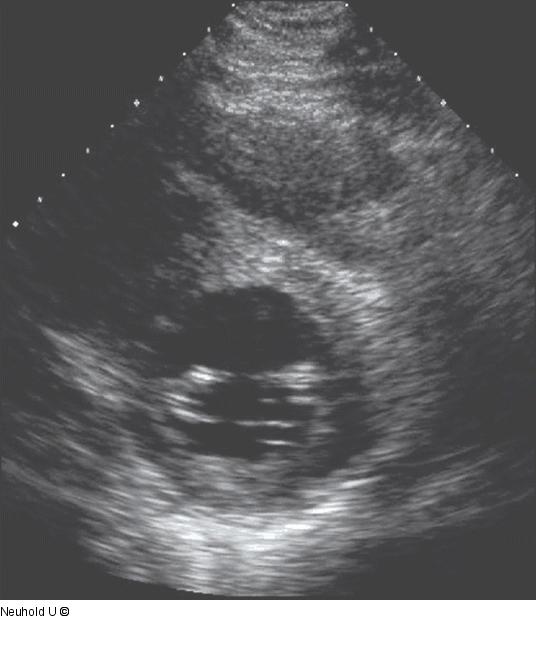

Abbildung 2: Mäßig reduzierte LVF Parasternal kurze Achse (=Querschnitt): mäßig reduzierte LVF |

Parasternal kurze Achse (=Querschnitt): mäßig reduzierte LVF |